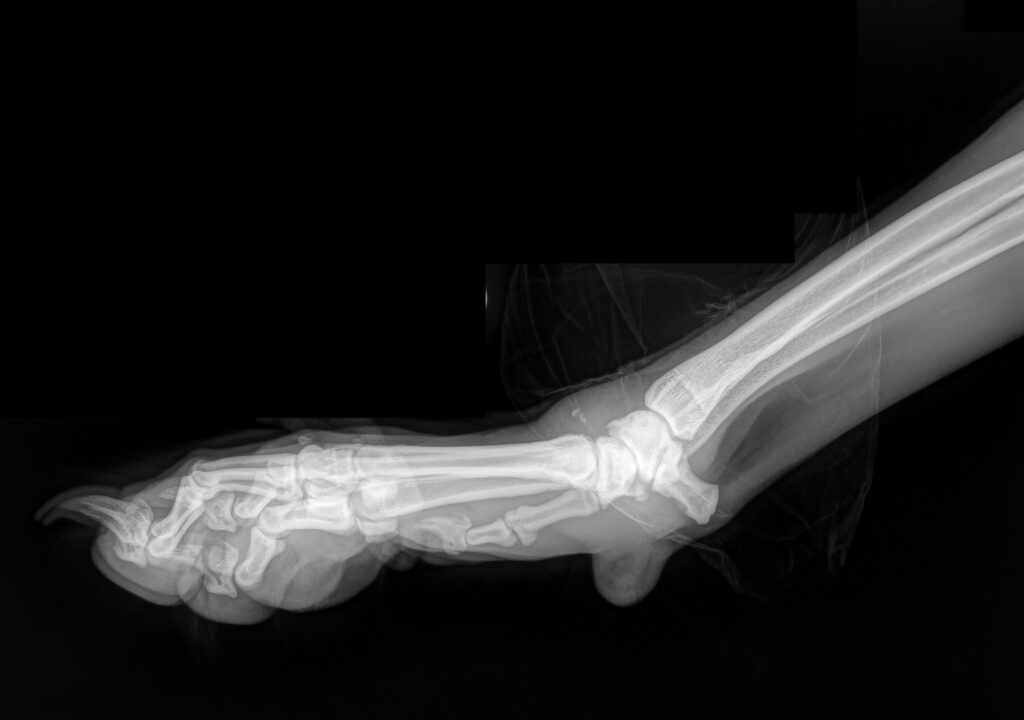

Forelimb

Conditions affecting the forelimb, including the shoulder, elbow, and wrist joints.